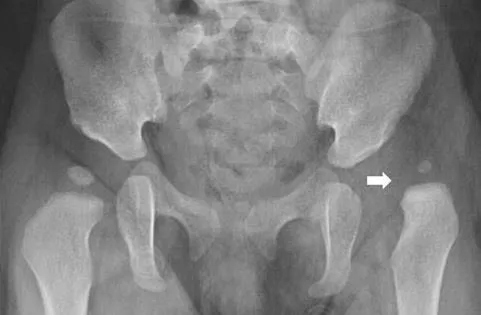

고관절 질환 3. 대퇴골두 무혈성 괴사증

소켓 모양의 고관절에 맞물리는 둥근 모양의 대퇴골두가 혈액 순환 문제로 뼈 조직이 괴사하는 질환이며, 대퇴골두 무혈성 괴사가 주요 원인입니다. 주로 30~50대에 나타나며, 남성의 발병률이 여성보다 높습니다. 약 60%가 양측성으로 나타나고, 주된 원인은 기저 질환으로 인한 코르티코스테로이드의 장기 사용과 과도한 알코올 섭취로, 전체 사례의 약 90%를 차지합니다.

괴사의 크기가 작고 통증이 일상생활에 큰 영향을 주지 않는 초기에는 약물 치료와 경과 관찰을 통해 관리하는 것이 좋습니다.

질환이 더 진행될 경우, 감압 수술은 괴사 부위의 압력을 낮추고 정상적인 혈액 공급을 회복하는 데 효과적입니다. 관절 치환술은 나이에 관계없이 괴사 부위가 넓거나 초기 단계라도 심한 통증을 겪는 노인 환자에게 특히 유용합니다.